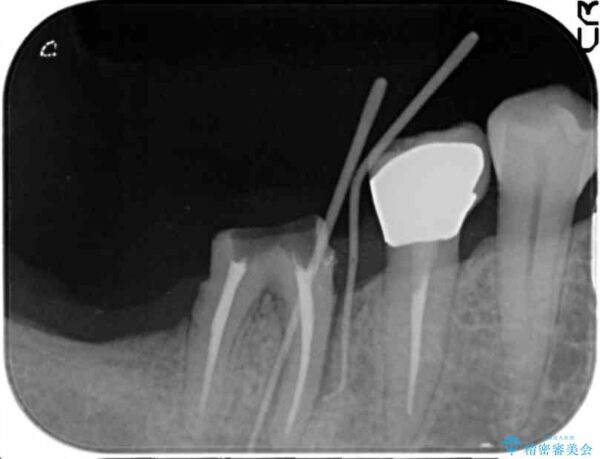

治療中

奥歯から膿のにおいがする インプラントによる機能回復 治療中画像 奥歯から膿のにおいがする インプラントによる機能回復 治療中画像 奥歯から膿のにおいがする インプラントによる機能回復 治療中画像 奥歯から膿のにおいがする インプラントによる機能回復 治療中画像

精査した結果、奥歯の根は破折しており抜歯を避けられない状況でした。

咬合力が強く、その他の歯の破折も防ぐために奥歯の咬合機能をインプラントを用いて回復する治療計画を立てます。